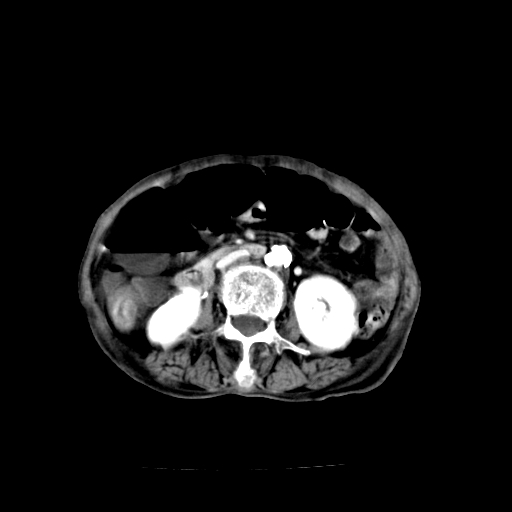

标题: CT19149:女,68岁,腹胀、恶心两周。 [打印本页]

女,68岁,腹胀、恶心两周,先做ct平扫,当时家属不同意强化,6天后家属要求增强扫描。

1、胃窦癌; 2、局灶性脂肪肝。

1、胃窦癌?建议行胃镜!; 2、局灶性脂肪肝。

1)不排除胃窦癌;建议行胃镜检查。 2)局灶性脂肪肝。腹水。

考虑:胃窦ca,腹水,脂肪肝

1)胃窦壁厚,考虑胃窦癌?建议行胃镜检查。 2)局灶性脂肪肝。

不均匀脂肪肝,胃腔改变须结合钡餐或胃镜观察